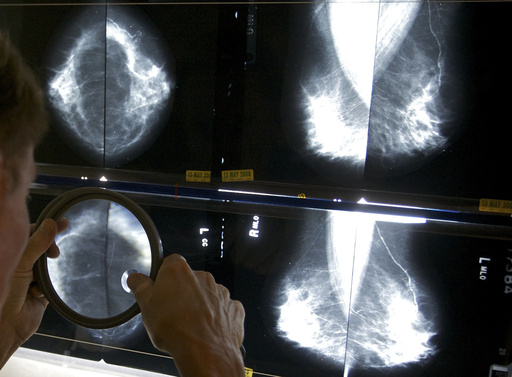

Regular mammograms to screen for breast cancer should start younger, at age 40, according to an influential U.S. task force. Women ages 40 to 74 should get screened every other year, the group said.

Age 40 is when mammograms should start for women, transgender men and nonbinary people at average risk. They should have the X-ray exam every other year, according to the new guidance. Other groups recommend annual mammograms, starting at 40 or 45.